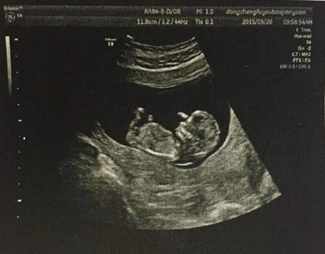

以灰阶即亮度(brightness)模式形式来诊断疾病称“二维显示”,因亮度第一个英文字母是B,故称B超,又称二维超声或灰阶超声。

B型超声是医学影像学超声的主要检查方法,虽然超声的发展突飞猛进,如内镜超声、超声造影、三维成像、弹性成像等等,都是在B型超声基础上发展起来的。因此,凡是进行超声工作的医师及被检查的患者,都应该了解B型超声的临床医学特点、检查前准备、检查范围及注意事项等等,以便更好地应用它来为被检查者服务服务。